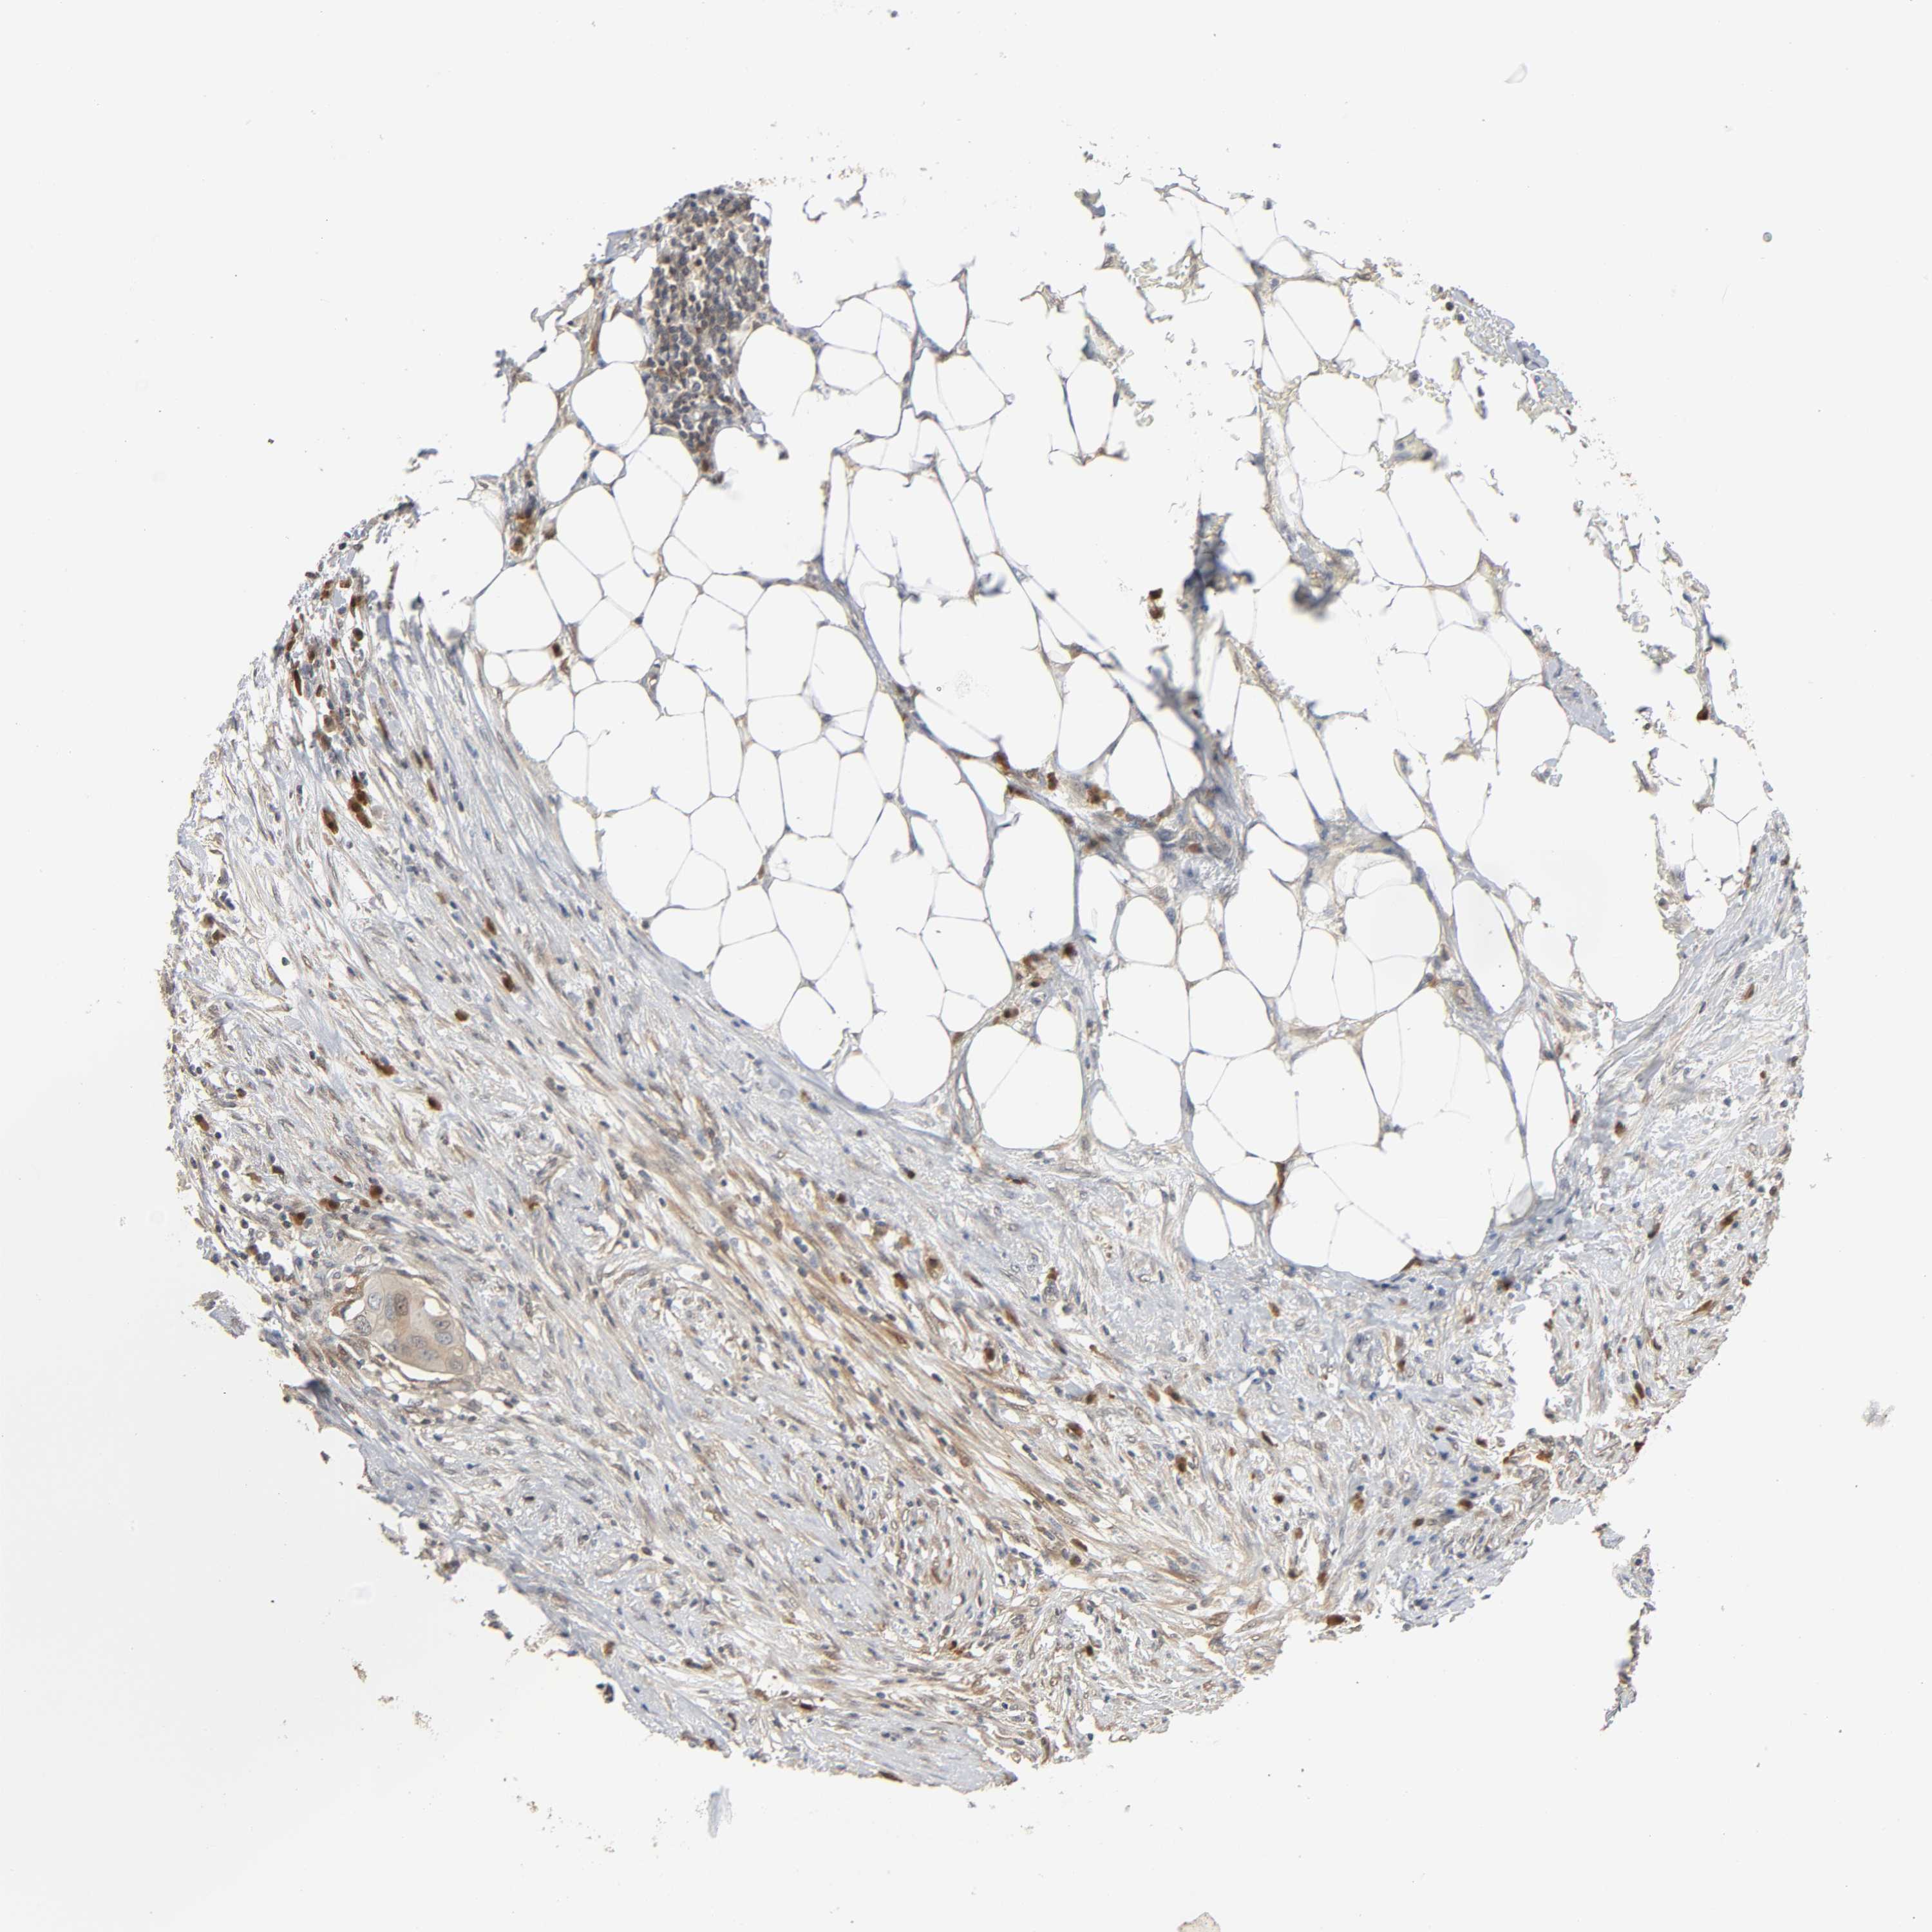

Number of samples 207

Samples

Sample Description pTPM